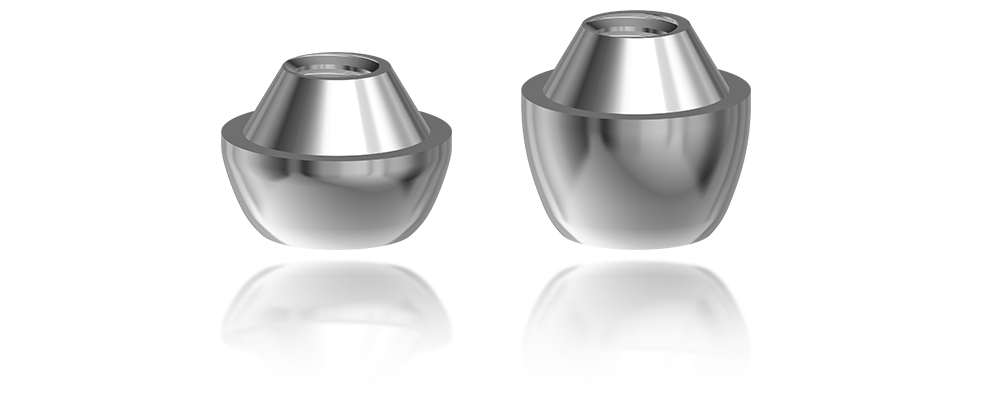

L’implant twinKon® est un implant type Tissue Level.

Sur le plan parodontal, la gestion du profil d’émergence a été revisitée de façon à favoriser le réaménagement d’un joint muqueux épais de première intention qui a vocation à jouer le rôle de barrière naturelle.

L’implant twinKon® est de type Tissue Level, généralement apprécié pour leur capacité à préserver le capital osseux péri-implantaire(1), mais également pour leur accessibilité prothétique en bouche. Le twinKon® est un implant qui sera particulièrement apprécié en secteur mandibulaire présentant une atrophie allant de modérée à sévère.